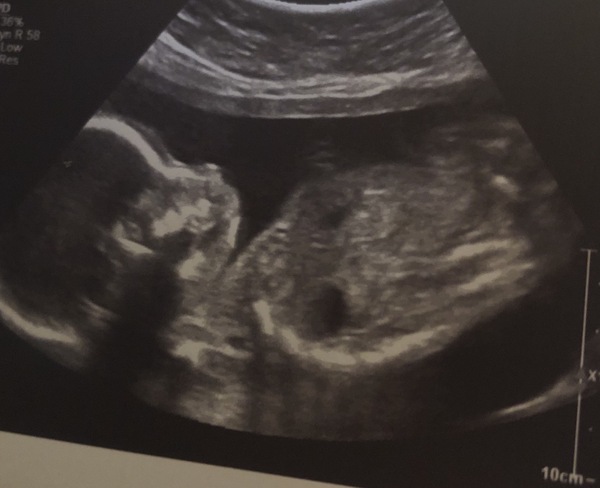

Here’s the pic from my scan yesterday. It’s a boy 💙